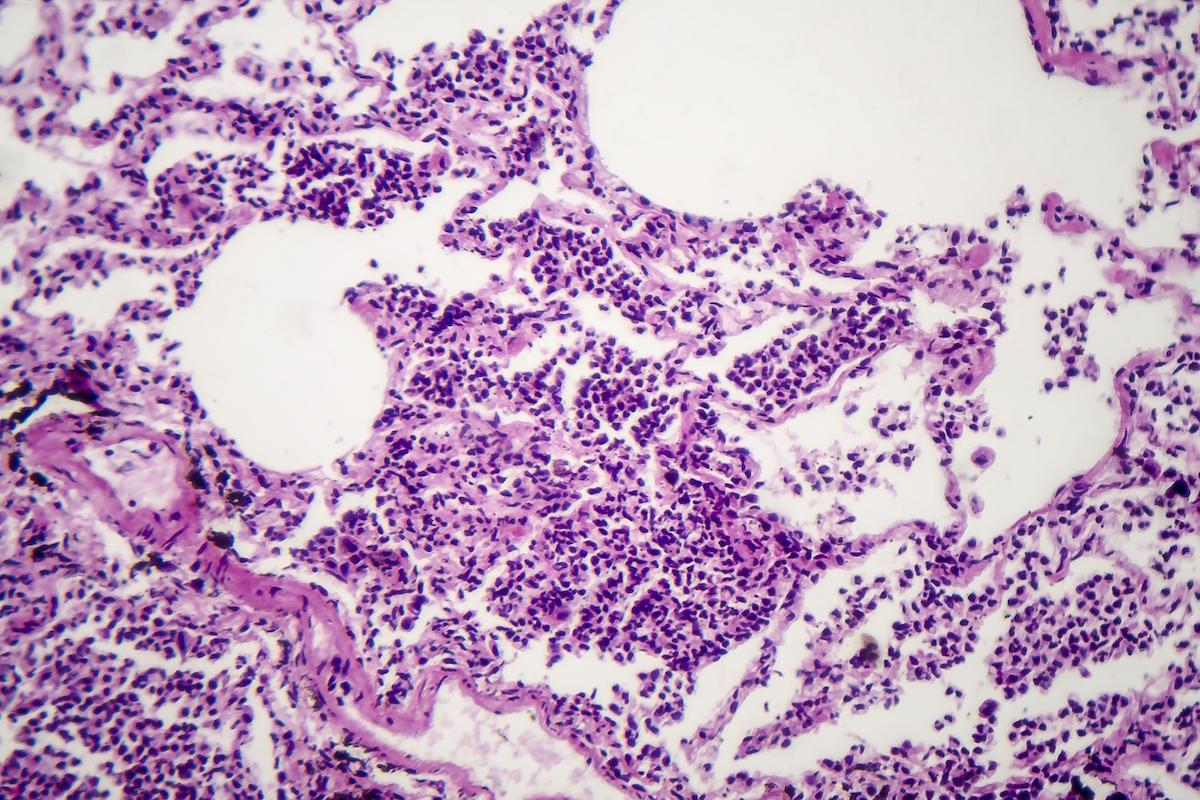

Pneumologie

Fibrose pulmonaire idiopathique : négativité de l’étude de phase 3 sur la zinpentraxine alpha

Malgré le bénéfice observé en essai de phase 2 de l’utilisation de la zinpentraxine alpha , l’essai de phase 3 n’a pas montré de bénéfices de la zinpentraxine alfa dans la fibrose pulmonaire idiopathique, avec des effets indésirables bien présents. Des résultats décevants et des explications données sur cette discordance…

Une étude dont les résultats sont parus en février 2024 dans l’American Journal of Critical Care Medicine, a cherché à évaluer l’efficacité de la zinpenraxine alpha chez les patients atteints de fibrose pulmonaire idiopathique. Il s’agit d’un essai de phase 3, en double aveugle, traitement versus placebo, multicentrique. L’essai de phase 2 avait retrouvé une amélioration clinique sur 28 semaines chez les patients recevant de la zinpentraxine alfa. La phase 3 a été réalisée dans 275 centres de 29 pays différents. Tous les patients étaient atteints de fibrose pulmonaire idiopathique et ont été randomisés :ils ont reçu soit une perfusion intra-veineuse de placebo soit une perfusion intraveineuse de 10 mg de zinpentraxine alpha, toutes les quatre semaines. La critère d’évaluation principal était l’amélioration de la capacité vitale forcée au terme de 52 semaines. Les critères d’évaluation secondaires l’amélioration en pourcentage de la capacité vitale prévue au bout de 52 semaines et le test de marche de 6 minutes. L’analyse des événements indésirables a également été réalisée.

Des résultats négatifs et une interruption prématurée

Au total, 644 patients ont été randomisés, dont 333 ont eu le placebo. Les résultats concernant la capacité vitale forcée ont été les mêmes a, au terme des 52 semaines, entre les patients ayant reçu le placebo et les patients ayant bénéficié de la zinpentraxine alpha. Les critères d’évaluation secondaires n’étaient pas non plus significativement différents. De plus, près de 75% des patients ont présenté au moins un événement indésirable. L’essai de phase 3 a donc été interrompu prématurément puisqu’aucun bénéfice de la zinpentraxine alpha n’a été démontré par rapport au placebo. Les auteurs de ce travail estiment que certains patients sous placebo, au moment de la phase 2, ont eu un déclin extrême, lié à la nature même de la maladie, qui a provoqué le bénéfice statistique de la zinpentraxine alpha, ce qui représente un biais dans les résultats de l’essai de phase 2.

Des résultats qui doivent faire réfléchir

Les résultats négatifs de l’essai de phase 3 viennent à l’encontre des résultats positifs et encourageants de l’essai de phase 2 et la conclusion est que le traitement par zinpentraxine alpha n’a pas d’intérêt dans la prise en charge de la fibrose pulmonaire idiopathique. Les auteurs de ce travail pensent qu’il est donc nécessaire de tirer une leçon afin d’améliorer les choix et les décisions concernant les essais thérapeutiques dans la fibrose pulmonaire idiopathique.

En conclusion, la zinpentraxine alpha n’a pas d’intérêt dans le traitement de la fibrose pulmonaire idiopathique malgré les espoirs initialement mis dans ce traitement. La tolérance n’est pas non plus au rendez-vous… Une réflexion vers d’autres essais thérapeutiques est nécessaire.